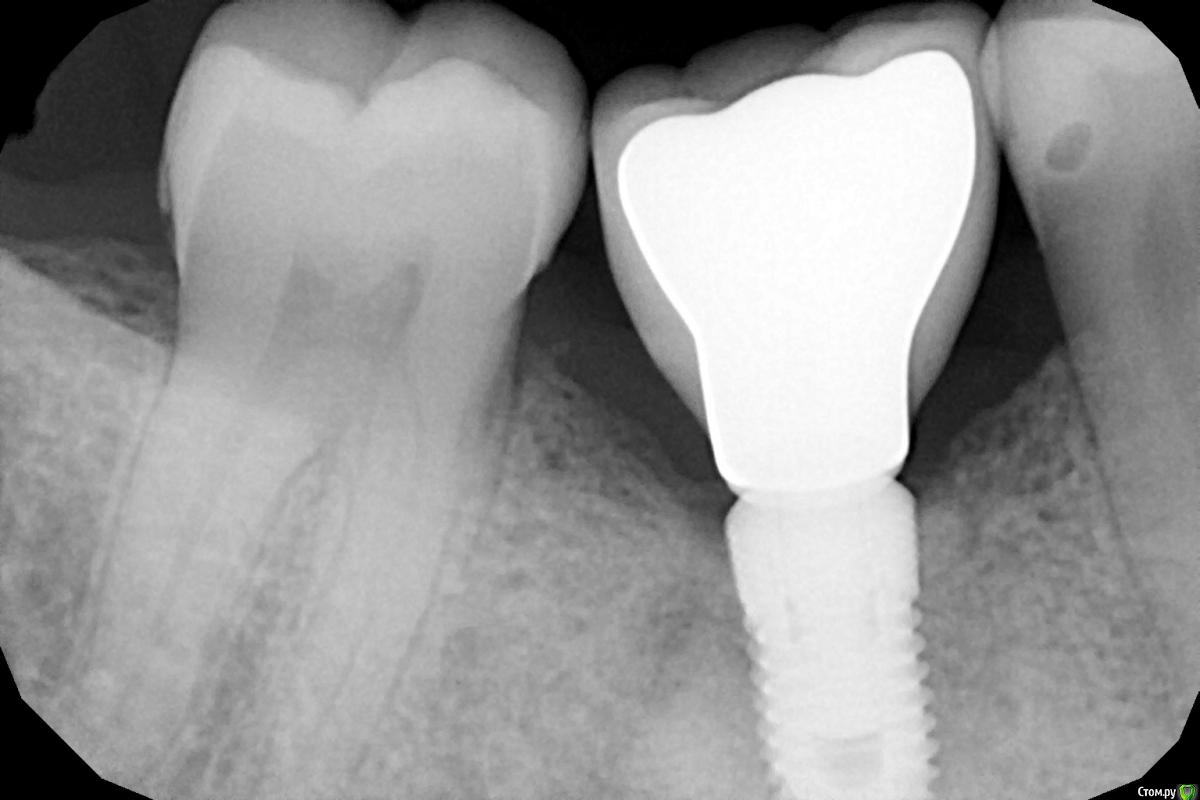

Irouil Опубликовано 9 декабря, 2020 Поделиться Опубликовано 9 декабря, 2020 (изменено) Рентген покажите с коронкой Изменено 9 декабря, 2020 пользователем Irouil 1 Ссылка на комментарий

Женька Опубликовано 10 декабря, 2020 Автор Поделиться Опубликовано 10 декабря, 2020 (изменено) Объясните пожалуйста, для чего нужен рг? Изменено 10 декабря, 2020 пользователем Женька Ссылка на комментарий

Irouil Опубликовано 10 декабря, 2020 Поделиться Опубликовано 10 декабря, 2020 Чтобы профиль прорезывания коронки понять, высоту основания. На мой взгляд (пусть меня поправят ортопеды, если что не так), тут надо было от основания еще резче расширить коронку. Надо объяснить технику, чтобы он не гнался за эстетикой, главная цель - ровное прилегание десны к коронке по кругу. Ну и дистально Вы там с сошлифовкой не перестарались, случайно? Контакт есть? Где забивается то пища у пациента? Я рекомендую еще в ортопедическом разделе спросить, но на мой взгляд в итоге все выглядит неплохо, направление верное, главное добиться нормальной гигиены. Ссылка на комментарий

Женька Опубликовано 10 декабря, 2020 Автор Поделиться Опубликовано 10 декабря, 2020 главное добиться нормальной гигиены.Это чтобы было чисто лишь усилиями пациента (неважно какими)или это чтобы хватало стандартных утро-перед сном чисток? Где забивается то пища у пациента? на осмотр пациентка пришла чистенькая. При том что она не знала, что будет простой осмотр, то есть вряд ли как-то особенно готовилась. Насколько я понял проксимально в промежутках...фотки мои к сожалению не информативны. И помимо этого в вестибулярной "нише" (не знаю как это место назвать) под коронкой. Но опять же, сам не видел. Пациентка внимания не заостряла на этом. И думаю, что не спроси я её об этом, она бы и не сказала ничего. тут надо было от основания еще резче расширить коронку Сошлифовывал ведь как раз из-за того, что посадить в шахту не мог на индексы шестигранника полностью. Если она будет еще шире всё снова ведь вернётся к сошлифовке. Контакт дистально точно есть! Ссылка на комментарий

Irouil Опубликовано 10 декабря, 2020 Поделиться Опубликовано 10 декабря, 2020 чтобы хватало стандартных утро-перед сном чисток? Этот вариантНасколько я понял проксимально в промежутках...фотки мои к сожалению не информативны. И помимо этого в вестибулярной "нише" (не знаю как это место назвать) под коронкой.Вестибулярно поднутрение. Вы писали, что посадить не получилось из-за наклона 4.7. Я это списал на дистальный контакт, а теперь Вы пишите, что просто не садилась коронка на индекс. Может стоило надрезать соединительно-тканное прикрепление при фиксации коронки? Вы же без временной коронки сажаете, представьте разницу между диаметрами ФДМ и профиля прорезывания коронки. Ссылка на комментарий

Женька Опубликовано 12 декабря, 2020 Автор Поделиться Опубликовано 12 декабря, 2020 Вы писали, что посадить не получилось из-за наклона 4.7. Я это списал на дистальный контакт, а теперь Вы пишите, что просто не садилась коронка на индекс. Может стоило надрезать соединительно-тканное прикрепление при фиксации коронки? Вы же без временной коронки сажаете, представьте разницу между диаметрами ФДМ и профиля прорезывания коронки.не совсем так, плохо объясняю значит, раз не поняли меня В общем. 4.7 наклон медиально, у 4.5 наоборот немного дистально. Выходит что с двух сторон поднутрения. В индексы, как я выразился, я не мог посадить как раз из-за этих поднутрений. Путь введения как бы вестибуло-оральный и шестигранник садится на индексы, но не полностью, тк мешали наклоны зубов... Ссылка на комментарий

Irouil Опубликовано 13 декабря, 2020 Поделиться Опубликовано 13 декабря, 2020 Все наоборот, это Вы меня не поняли, а я вот Вас понял сразу. Моя очередь оптимизировать объяснения: Я не предлагаю Вам делать трапецевидную коронку с широким основанием цервикально - тут дело ясное, что она не влезет между зубами. Я предлагаю придать ей близкую к прямоугольной форму, чтобы у шейки она была по ширине практически равна межзубному расстоянию 5-7 на уровне контактов. Для этого надо, чтобы от основания коронка начинала расширяться практически сразу. В конце концов, Ваша задача заполнить межзубные амбразуры, которые ещё и увеличены из-за наклона рядом стоящих зубов, а материала для заполнения у Вас меньше, из-за недостаточного заглубления. Так что резкое расширение коронки 1) заполнит часть этого пространства собой 2) отдавит больше пришеечных тканей латерально в область амбразур 1 Ссылка на комментарий